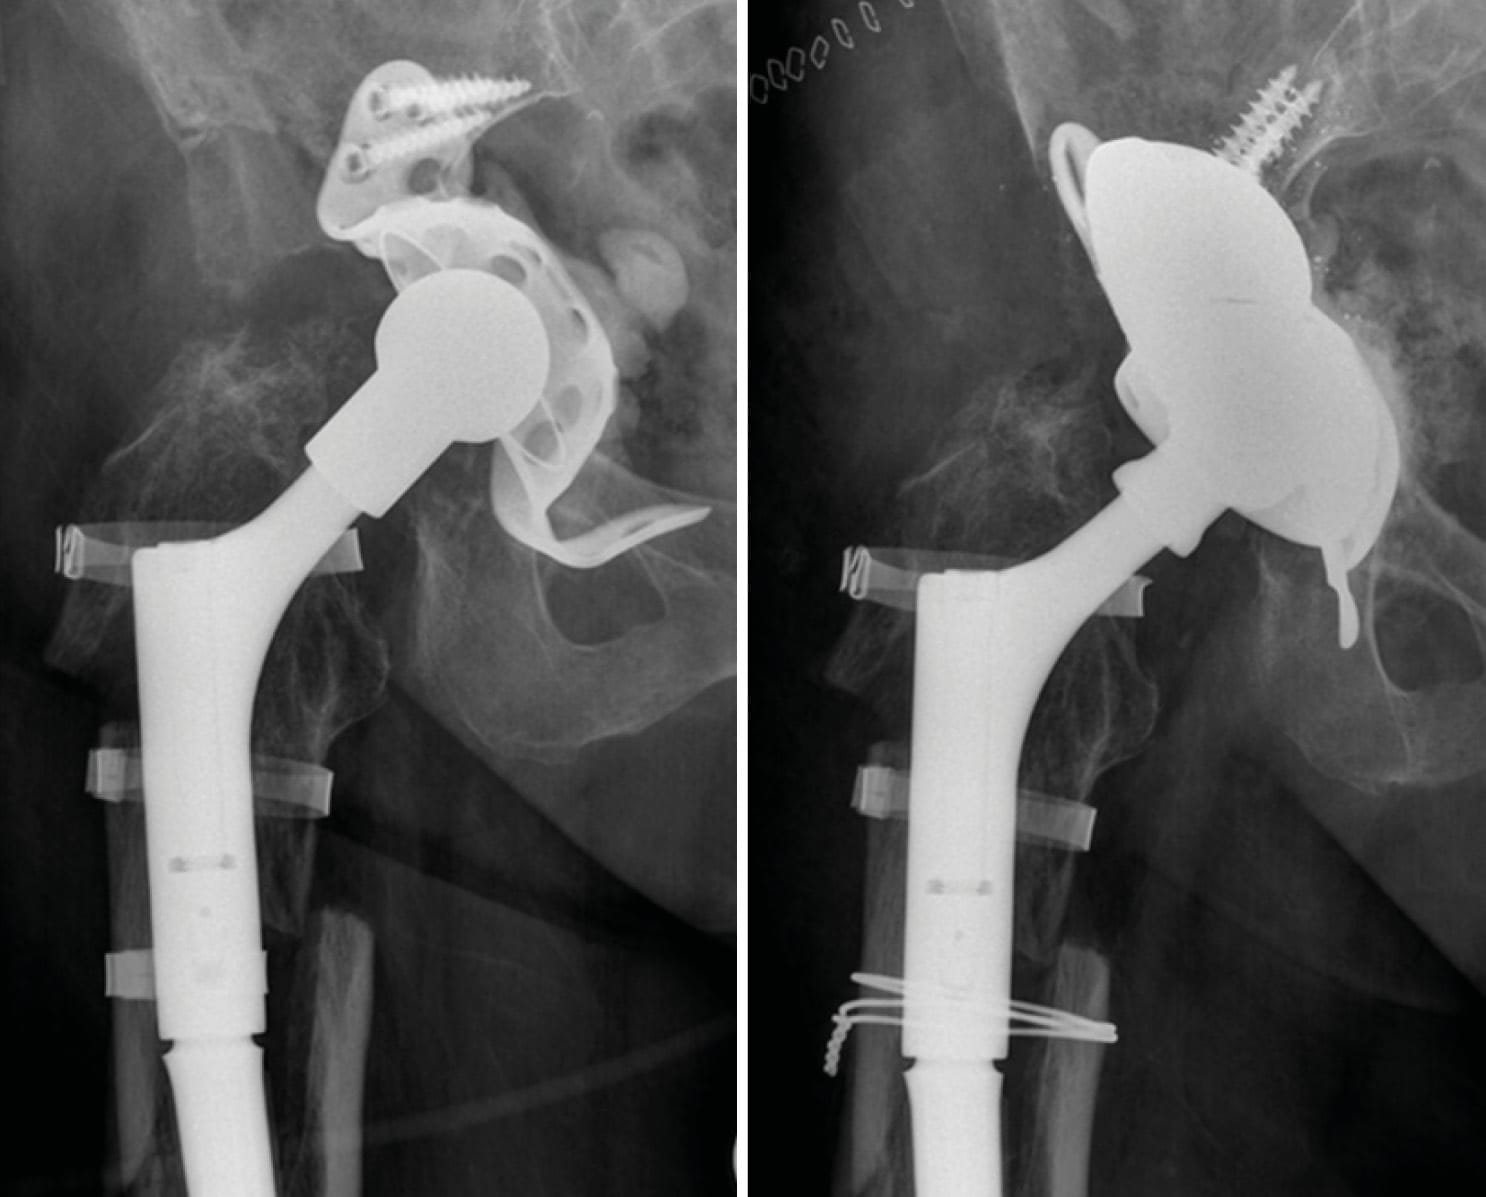

Case 5: Caution with application of extra-long adapters and modular revision stems (76-year-old male)

The patient had undergone femoral revision surgery due to aseptic stem loosening of the left hip 5 years ago. He subsequently developed failure of the taper junction of the modular revision stem. Most manufacturers advise against using heads larger than size L in combination with modular revision stems due to increased lever arms which may exceed material tolerance of taper connections.